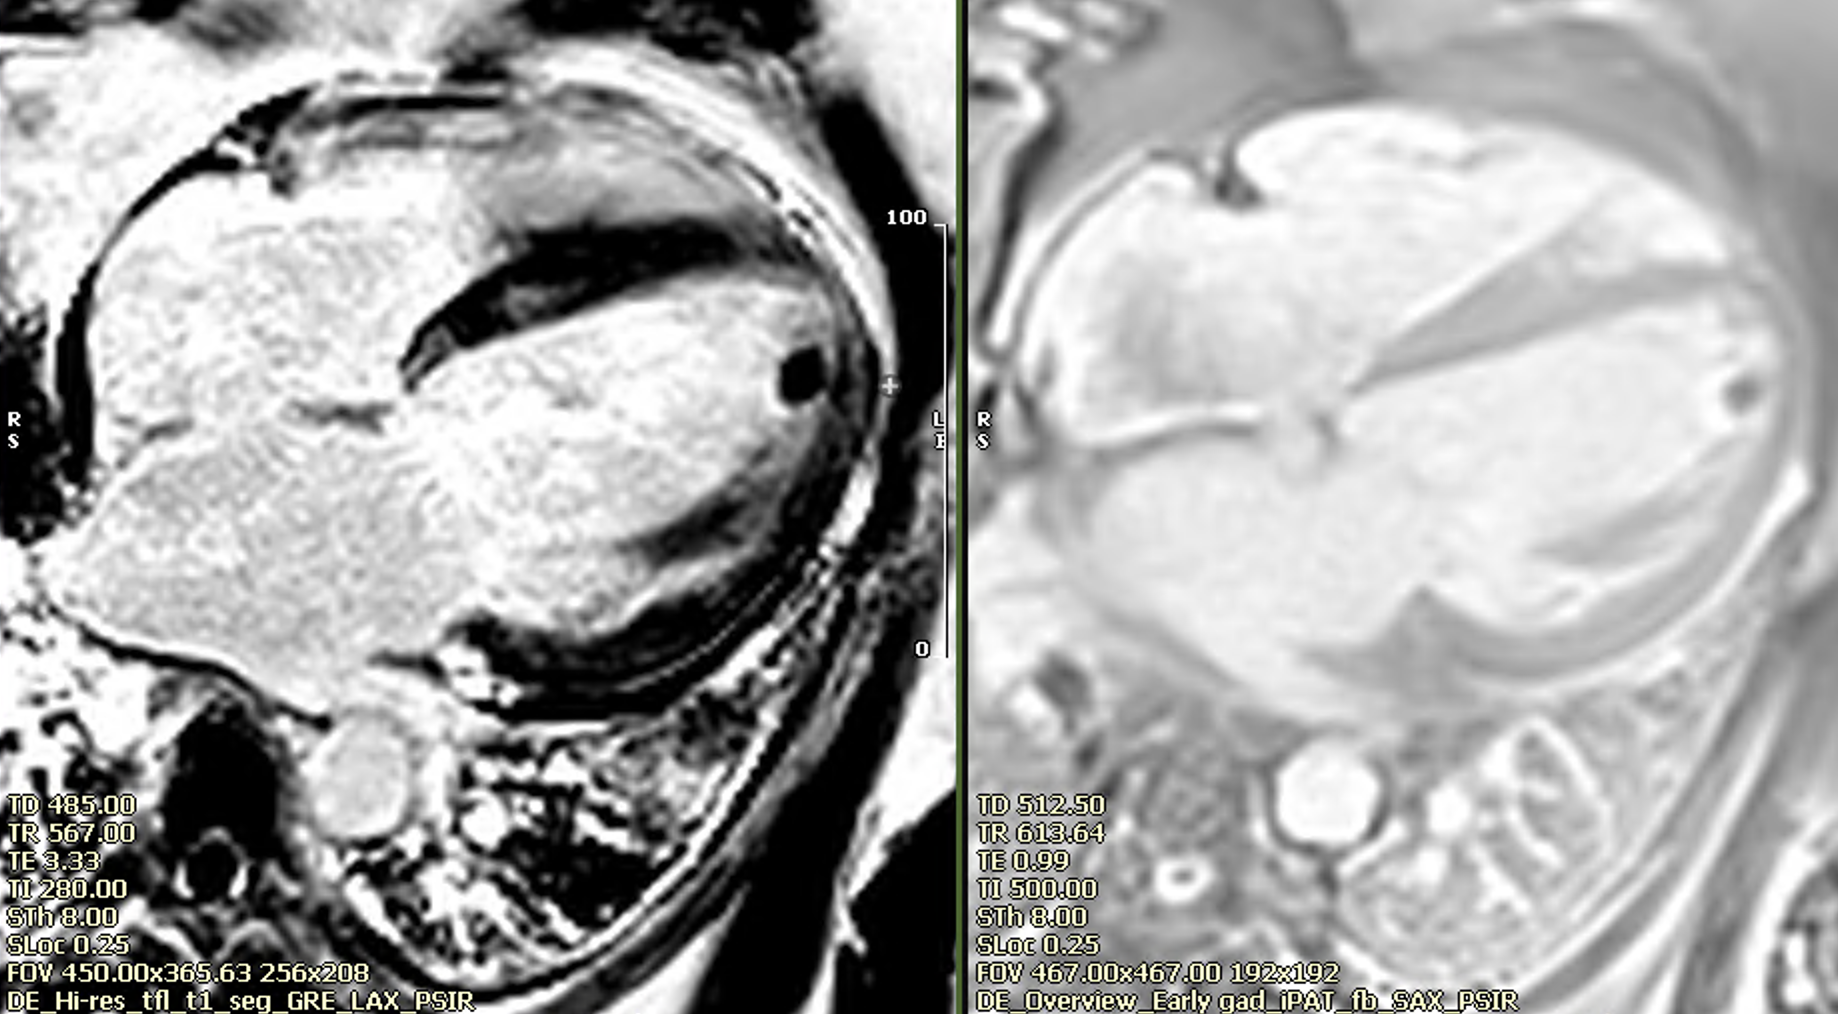

Non ischemic late enhancement (left panel), apical thrombus in early gad sequences (right panel).